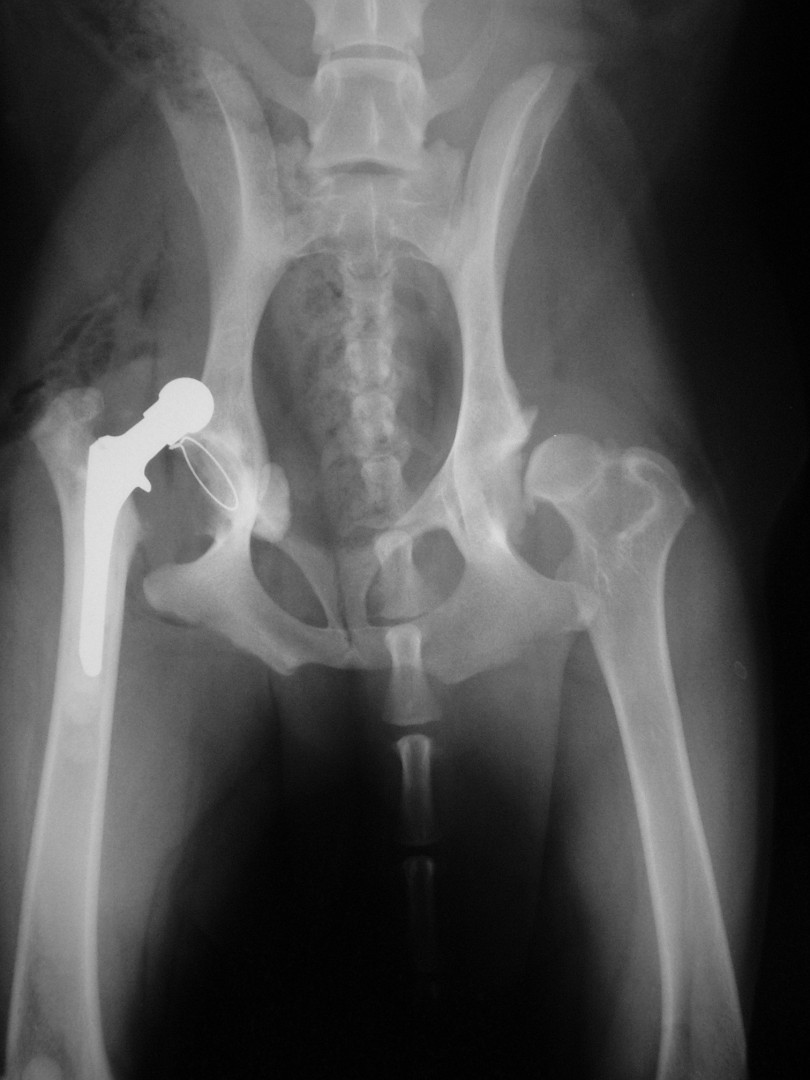

Bár a csípőízület megbetegedéseiről – mint a leggyakrabban tárgyalt ortopédiai megbetegedésről- első körben nem szerettem volna szólni, mégis megteszem, mert 2010. májusában egy hosszabb egyeztetést és szervezést követően beültettük az első teljes csípőízületi protézist…

A szervezés két részből állt: egyrészt felkerestük azt a magyarországi gyártót, aki a hazai anyagi lehetőségeket is figyelembe véve a szakmai szempontból is optimális rendszert le tudja gyártani, másrészt rábeszéltem Kendik Zsolt kollégámat, aki a hazai csípőízületi protézis beültetésének úttörője, hogy legyen segítségemre a műtét technikájának elsajátításában.

A tényleges műtét előtt temérdek teendő akad. A kutya teljes belgyógyászati kivizsgálása, egyéb ortopédiai és/vagy neurológiai betegségek kiszűrése, a tulajdonosokkal folytatott többszöri megbeszélés, a kockázatok mérlegelése és ezek részletes ismertetése jelentős energiát emészt fel. De ezek nélkül a beteg állat tulajdonosa nem tud reális döntést hozni: vállalható-e a műtét vagy sem?A műtéti időpont egyeztetése sem egyszerű: az operáció során 4 ember összehangolt munkájára, tökéletes aneszteziológiára és a műtétet követően az asszisztensek gondos munkájára van szükség a teljes gyógyuláshoz. Ez szintén jelentős szervezést igényel. A műtétet követő 10 napos kórházi ápolás és az ez utáni 3 hónapon át tartó szigorú mozgáskorlátozás betartása és betartatása a gyógyulás elengedhetetlen feltétele. Egy fiatal, ereje teljében lévő, energikus kutyánál ez néha nehezebb feladat, mint maga az operáció.

Az első műtét remekül sikerült és Connor, a skót juhász kutya megkapta a bal oldali új csípőízületét. A 7 napi kórházi tartás is problémamentesen zajlott és a varratszedés idejére a műtött végtag terhelése gyakorlatilag hibátlan volt. Az 1 hónapos és a 3 hónapos kontroll RTG vizsgálatokon sem jelentkezett szövődményre utaló jel, az 1 éves postoperatív időszakban már csak az látszott, hogy a műtött lábát jobban terheli, mint a nem operált végtagot. Így 2011. júniusában – immár sokadik csípőízületi protézis műtétként- a jobb oldali csípőízületét is megoperáltuk. Connor gyakorlatilag azóta teljes életet él és vidáman játszik társaival, még birkákat is terel…A majd két éves, a protetizálás során szerzett tapasztalatok azonban nálunk is hozzák a szakirodalomban leírt szövődményi lehetőségeket és arányokat. Leggyakrabban a beültetett protézis ficamával találkoztunk, de akadt sajnos kilökődési reakció is. Ezen problémák – az előzetes tájékoztatás ellenére is- mindig váratlanul érik a tulajdonost és az állatorvost egyaránt. Megoldásuk szinte kizárólag műtéti, ami újabb kockázatot, újabb fizikai és anyagi áldozatot jelent.